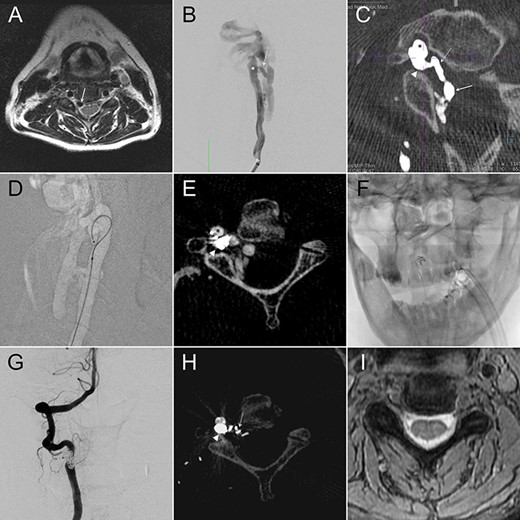

A 58-year-old female had a descent injury 5 months earlier. One month later, she started to have right C5 radicular pain and progressive weakness in elbow flexion. Cervical magnetic resonance (MR) imaging revealed an enlarged flow-void signal near the right C4–5 intervertebral foramen (Fig. 1A). In 2D-DSA of the right VA, a high-flow fistula connecting the right distal AV and the paravertebral vein was detected at the right C2–3 level (Fig. 1B). IA-CBCTA further delineated that the fistula connected the VA to a venous channel inside the foramen transversarium, which in turn drained through the intervertebral foramen and reached the intraspinal epidural space (Fig. 1C). We therefore set the venous compartment inside the foramen transversarium as our embolization target and spared the rest of the drainage veins.

We navigated the microcatheter (Fig. 1D) and placed a framing coil into this target. This first coil, as confirmed of its proper position by another IA-CBCTA (Fig. 1E), served as the frame for our following coiling procedure (Fig. 1F). As shown in the postop 2D-DSA and IA-CBCTA, VVF was completely obliterated, and the dense coil mass was exclusively located within the foramen transversarium, except for a single coil loop within the downstream vein (Fig. 1G and H). The patient’s neurological deficits recovered gradually, and the epidural flow-void signals disappeared in the postop MR (Fig. 1I).

(A) Cervical MR revealed an enlarged epidural flow-void signal near the right C4–5 intervertebral foramen. (B) Anteroposterior (AP) view of the right VA angiography demonstrated a high-flow VVF at the C2–3 level. (C) An oblique axial reconstruction of IA-CBCTA revealed the detailed angioarchitectural arrangement of the VVF, as well as its anatomical relations to the foramen transversarium, intervertebral foramen and the spinal canal. The proposed embolization target for dense coil packing was limited to the venous channel outside the intervertebral foramen. (D) Roadmap fluoroscope demonstrated the position of the microcatheter tip within the target. (E) IA-CBCTA performed after placing one framing coil confirmed the proper position of the coil. (F) This first coil therefore served as the frame for the following dense coiling under fluoroscopy. (G) AP view of the control right VA angiography demonstrated complete obliteration of the VVF. (H) Postop IA-CBCTA demonstrated the dense coil mass within the foramen transversarium, and a single coil loop within the intervertebral foramen. (I) Postop MR showed disappearance of the engorged epidural venous channels. Arrowhead, drainage vein within the foramen transversarium (the embolization target for dense coiling); Asterisk, right VA; dashed arrow: drainage vein within the intervertebral foramen; Solid arrow, drainage vein within the spinal canal.